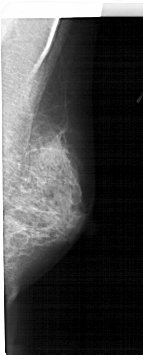

A_1609_1.RIGHT_MLO

RIGHT_CC LINES 3676 PIXELS_PER_LINE 1771 BITS_PER_PIXEL 12 RESOLUTION 43.5 NON_OVERLAY

RIGHT_MLO LINES 5311 PIXELS_PER_LINE 2131 BITS_PER_PIXEL 12 RESOLUTION 43.5 NON_OVERLAY